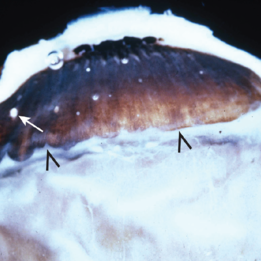

Intermediate Uveitis

Intermediate Uveitis

May 18 2020 by McGill University Health Centre

This enucleation specimen shows: “snowballs” or localized inflammatory foci (arrow); and a “snow bank” or inflammation at the ora serrata, the anterior-most limit of the retina. These are caused by a reaction to the subjacent uveitis (arrowhead).

Condition/keywords: intermediate uveitis